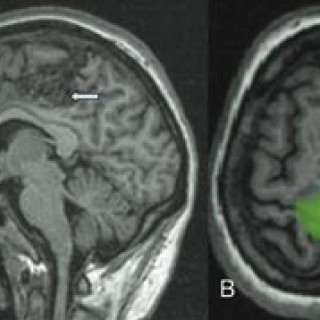

Nevroradiologi omhandler bildediagnostikk av og bildeveiledet intervensjon i sentralnervesystemet. Pasientene er i alle aldersgrupper, og flere av sykdommene er kroniske. Kunnskap om barnenevroradiologi er vesentlig for forståelsen av mange lidelser hos voksne. De viktigste bildediagnostiske hjelpemidlene (modalitetene) er CT, MR og angiografi, i tillegg til vanlig røntgen, myelografi, ultralyd, scintigrafi og positronemisjonstomografi (PET). Faget er en naturlig subspesialisering fra generell radiologi, med bakgrunn i behovet for oppbygging av kompetanse om og utvikling av høyspesialiserte...